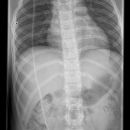

Shuntverlauf

Es wurden keine Bilder gefunden.

Technik

FDA: 1,15 m

Ausgangsformat: je nach Körperregion

mit Raster

Indikation

Shuntkontrolle

Lagerung

1. Schädel/HWS ap

Patient in Rückenlage, Kinn anziehen lassen, 15° Keil unter den Kopf, so dass Deutsche Horizontale (DH = Frankfurter) senkrecht zum Film steht, Kopf muss seitengleich, symmetrisch gelagert werden.

2. Schädel/HWS seitlich

Patient in Rückenlage, Kopf auf die rechte Seite drehen und Medianebene verläuft parallel zum Tisch, Stirn-Augenbrauen-Linie verläuft senkrecht und die Stirn-Kinn-Punkte verlaufen parallel zur Filmeinblendung. Der Körper dreht sich somit etwas auf die rechte Seite.

3. Thorax/Abdomen

Patient in Rückenlage, Arme am Körper entlang, Beine geschlossen.

4. evtl Becken

Patient in Rückenlage, Beine leicht gespreizt.

Zentralstrahl

Senkrecht auf Objekt, vom Schädel bis Abdomen müssen alle Bilder überlappend sein.

Variante

Abdomen evtl seitlich röntgen, wenn die Shuntlänge 3-4cm unterhalb der Markierung ist (nicht mehr im kleinen Becken) -> Belichtung dann wie seitliche Wirbelsäule.

Anmerkung

Die Stelle (Narbe) an der der Shunt in dem Abdomen verschwindet, muss mit einer Metallkugel etc. markiert werden.